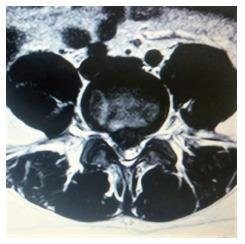

Transforaminal Percutaneous Endoscopic Discectomy (TPED) is a minimally invasive technique mainly used for the treatment of lumbar disc herniation from a lateral approach. Performed under local anesthesia, TPED has been proven to be a safe and effective technique which has been also associated with shorter rehabilitation period, reduced blood loss, trauma, and scar tissue compared to conventional procedures. However, the procedure should be performed by a spine surgeon experienced in the specific technique and capable of recognizing or avoiding various challenging conditions. In this review, pitfalls that a novice surgeon has to be mindful of, are reported and analyzed.

经椎间孔入路经皮内镜下椎间盘切除术(TPED)是一种主要用于从侧方入路治疗腰椎间盘突出症的微创技术。TPED在局部麻醉下进行,已被证明是一种安全有效的技术,与传统手术相比,它还具有康复期短、失血少、创伤小和瘢痕组织少的特点。然而,该手术应由精通该特定技术且能够识别或避免各种具有挑战性情况的脊柱外科医生进行。在本综述中,报告并分析了新手外科医生必须注意的陷阱。